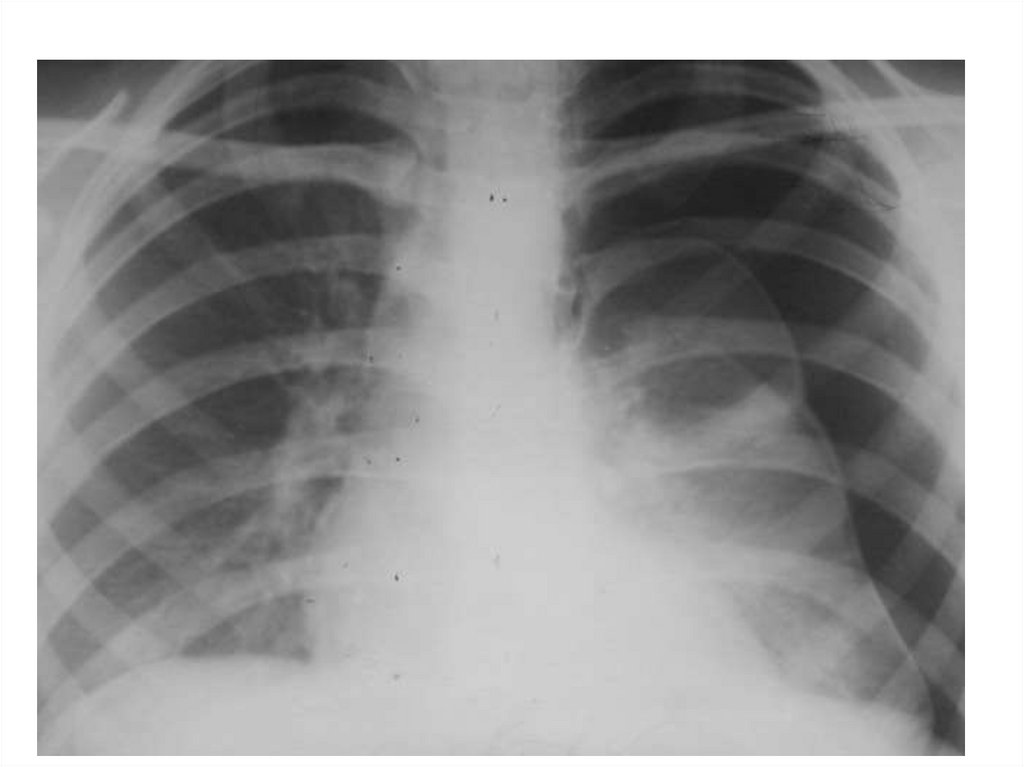

Экссудативный плеврит